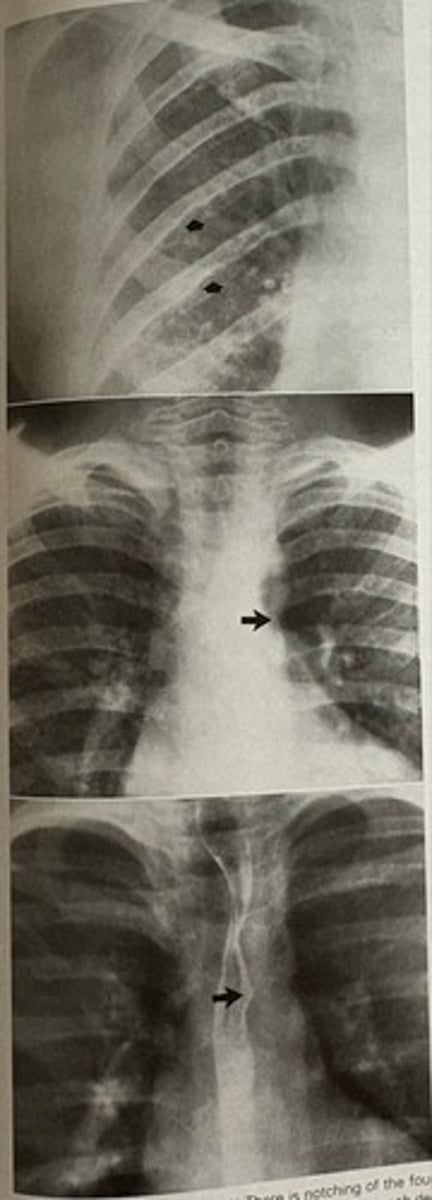

coarction of the aorta

what pathology is present?